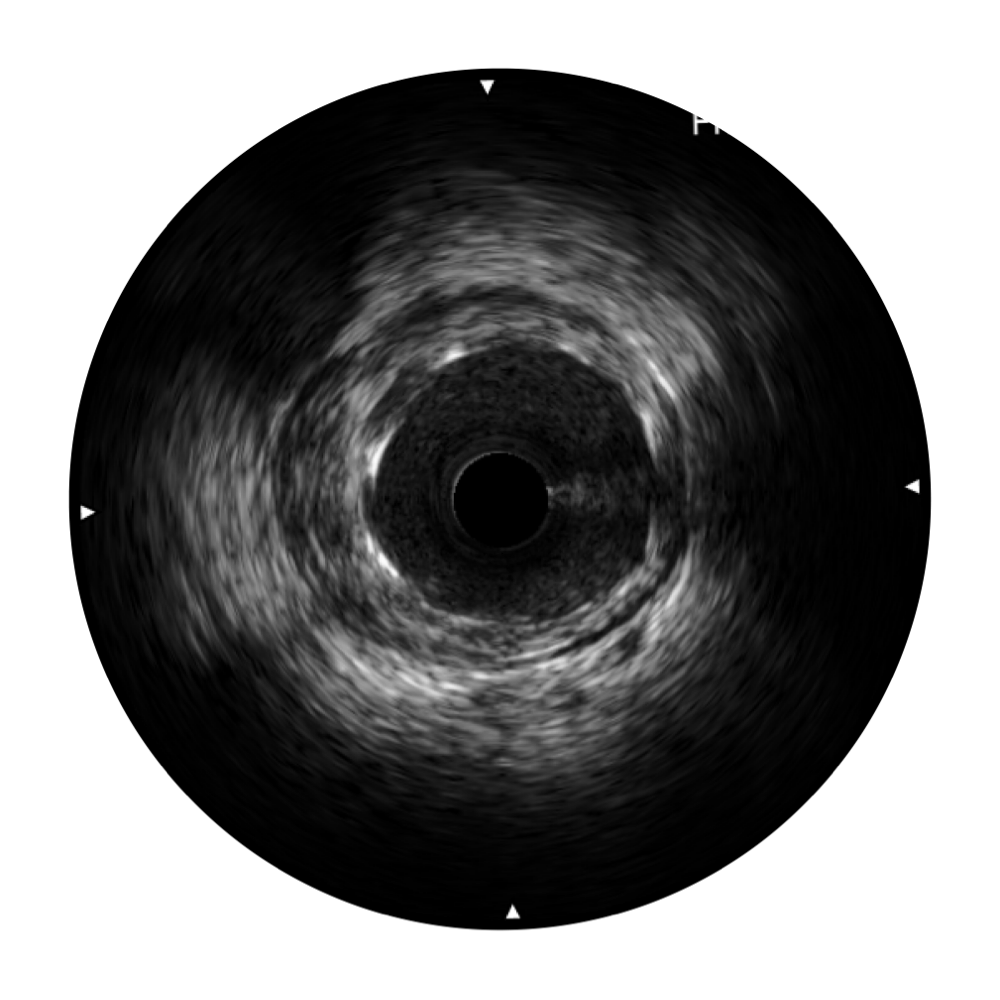

• 米兰官方网站宽频IVUS图像

对比传统IVUS导管成像,米兰官方网站宽频IVUS图像的近场支架梁显影更细腻,远场中膜外血管仍清晰可辨,兼顾远中近,兼顾分辨力与穿透深度